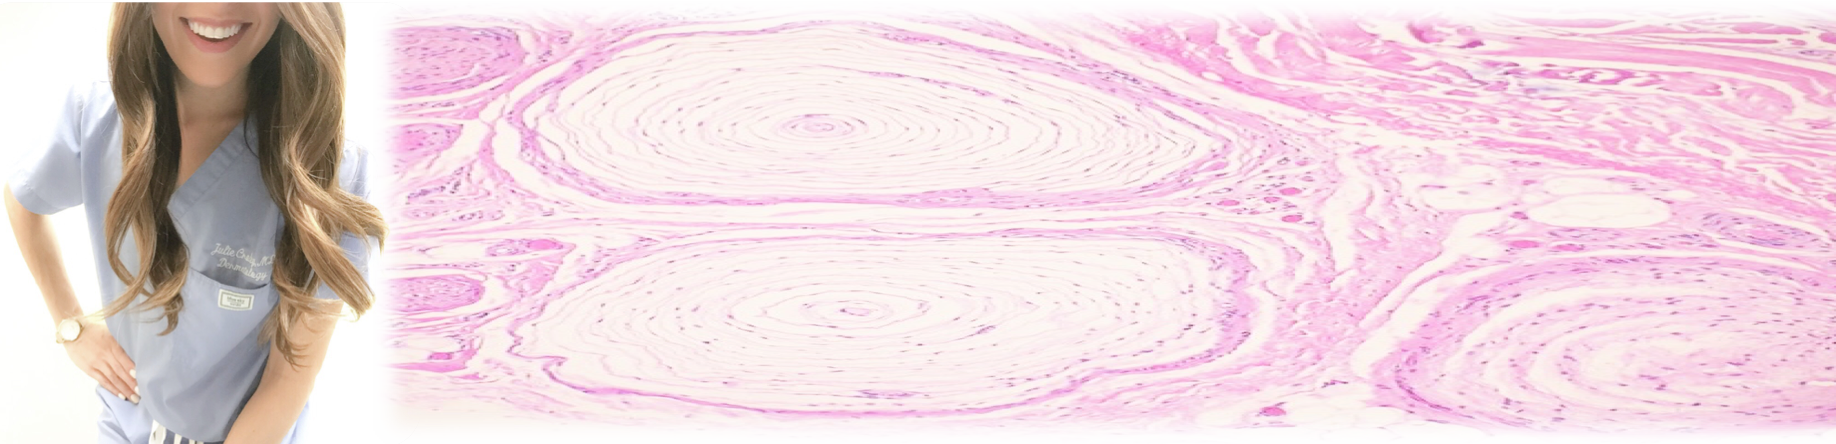

Screen Shot 2018-01-07 at 2.42.17 PM